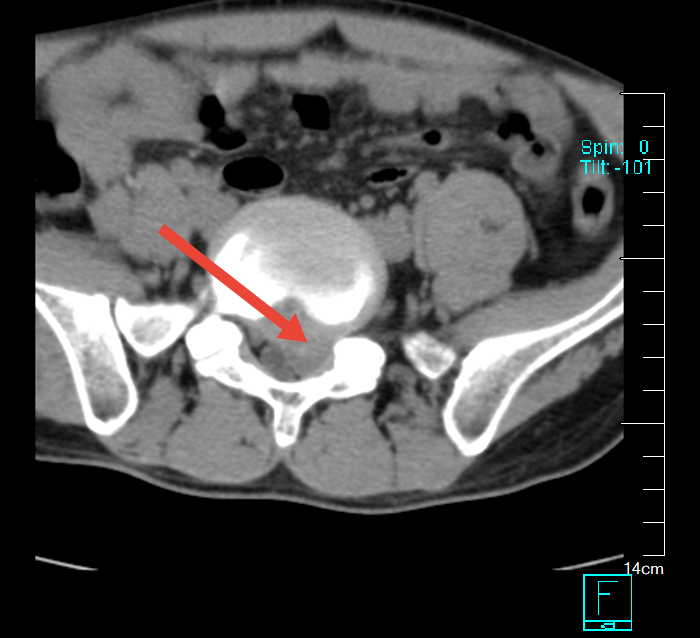

術前